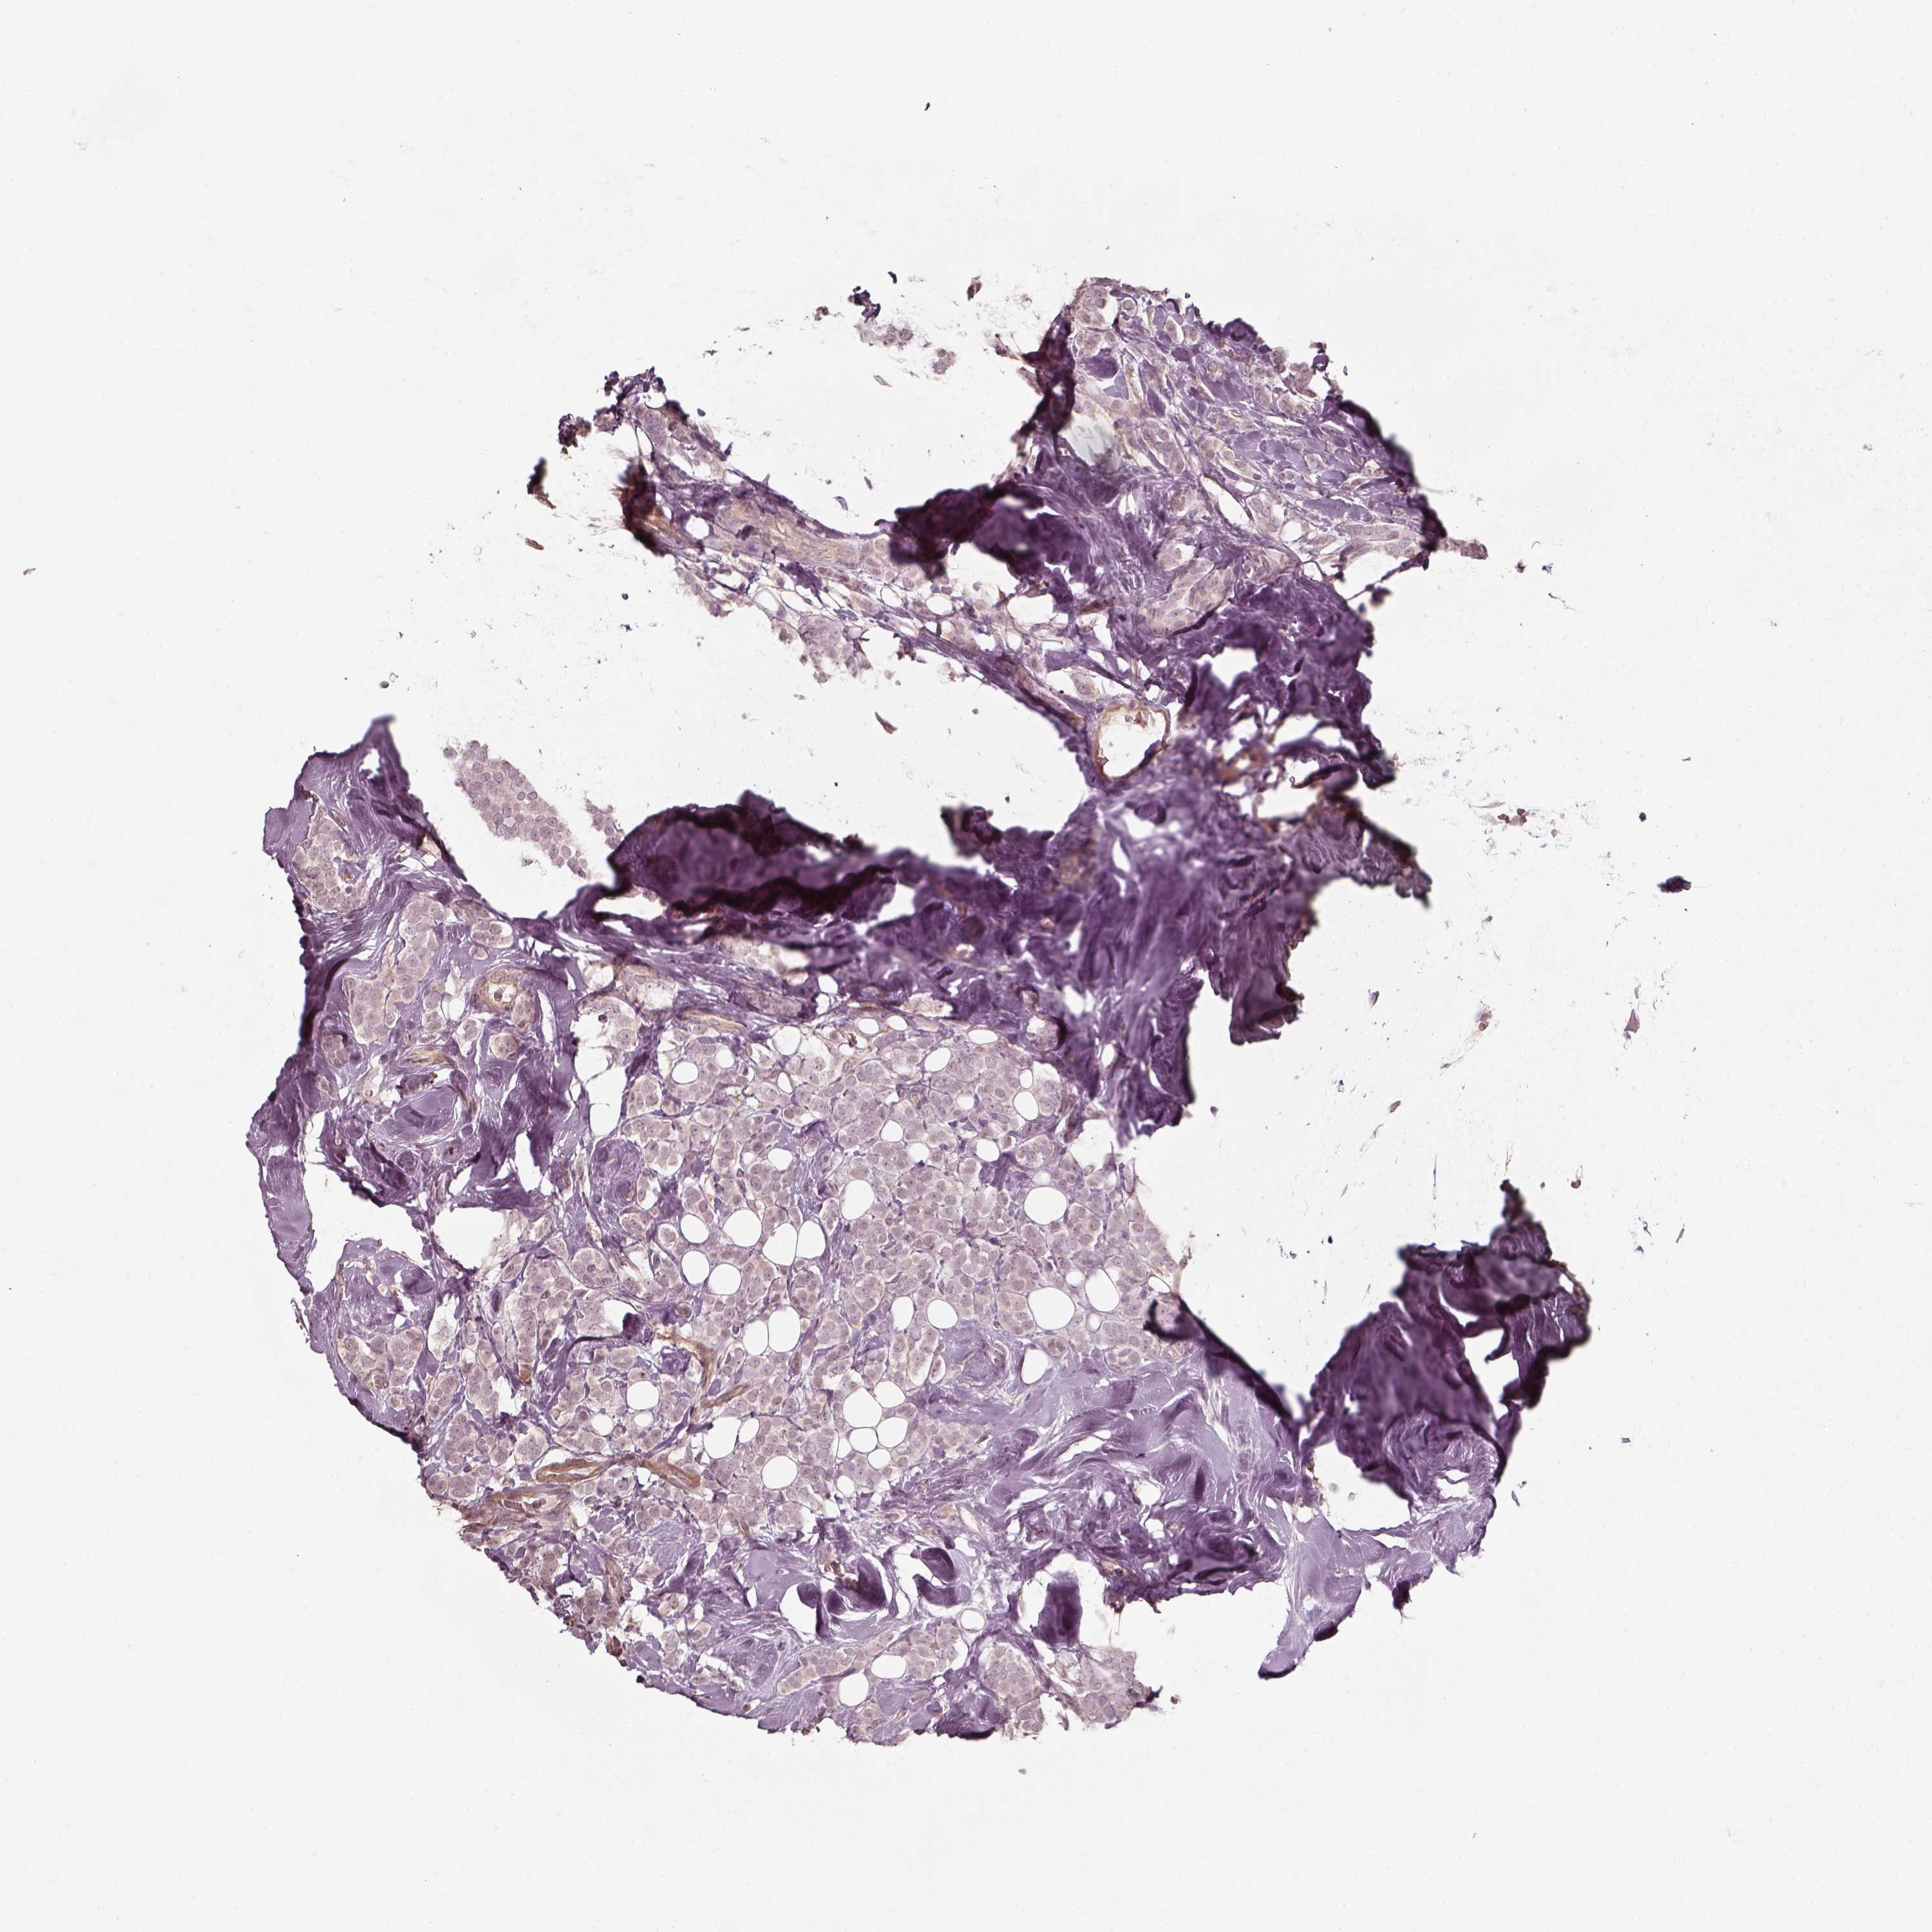

CANCER BREAST CANCER Show tissue menu

Breast cancer

Human cancer